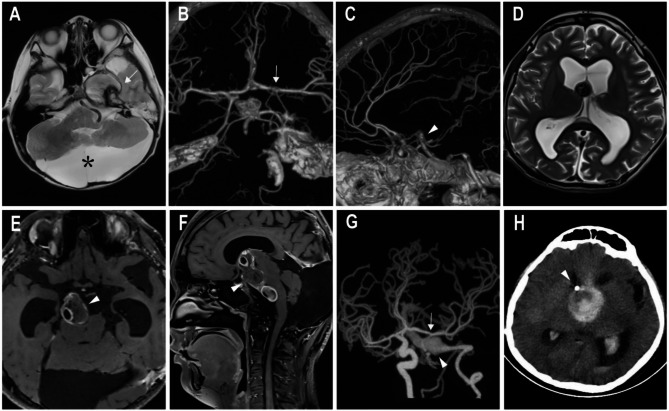

Case presentation: In the first case, a 15-year-old boy initially presented in July 2020 with recurrent mild nausea and vomiting. He was diagnosed with left internal carotid artery (ICA) occlusion secondary to a giant fusiform aneurysm, along with a cerebellar arachnoid cyst. The patient received conservative treatment but did not adhere to the recommendation for regular follow-up. In August 2023, he developed hydrocephalus and severe brainstem compression caused by VBD. Ventriculoperitoneal (V-P) shunting failed to prevent rapid clinical deterioration, which eventually led to fatal intracranial hemorrhage. The second case involved a 9-year-old boy who initially presented in June 2013 with hydrocephalus and underwent V-P shunting. In June 2020, he was diagnosed with right ICA dolichoectasia during an evaluation for neck discomfort and subsequently underwent ligation of the right ICA. In March 2022, he experienced an acute onset of altered consciousness, and neuroimaging confirmed brainstem compression due to VBD. Considering the high anesthetic risk and the limited potential benefit of further surgical intervention, treatment was withdrawn, and the patient ultimately died of brainstem infarction.